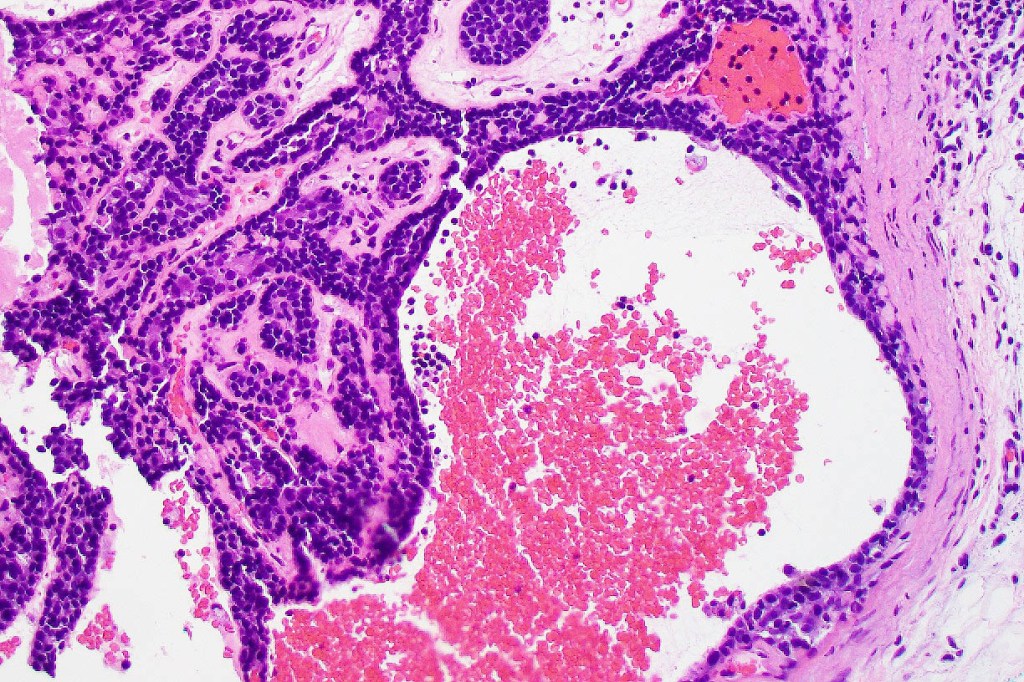

•Nodule/multiple blue encapsulated nodules in the dermis +/- subcutaneous fat

•Common association with an adjacent nerve & exceptional intraneural component

•Marked lymphedema sometimes present- lymphangiectatic variant

•Telangiectatic variant